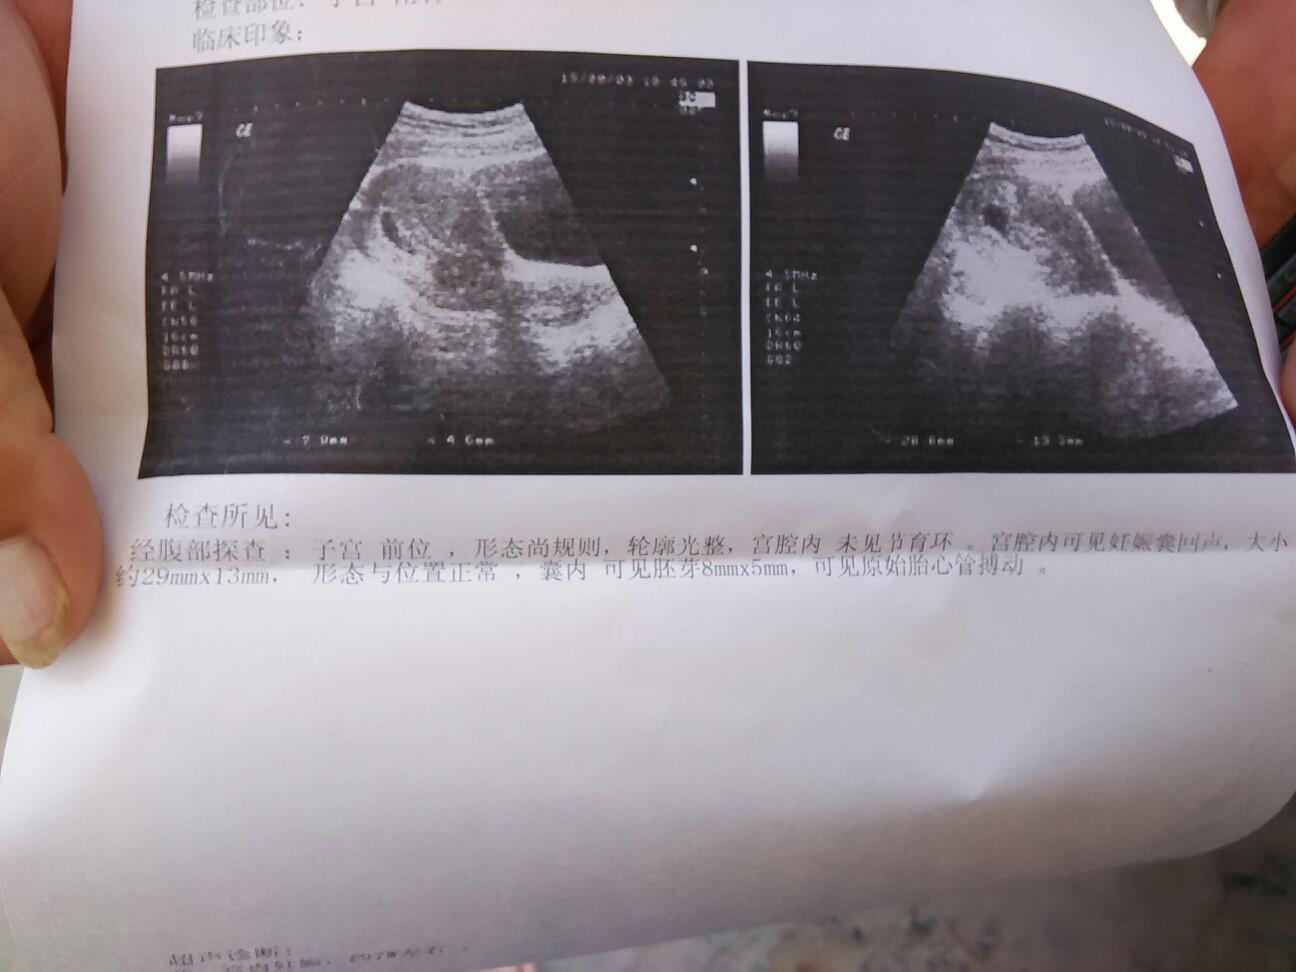

每次去检查都是我一糟菜个人去。坐公交车来来回回。颠死我了。医生还说我要保胎。打印趋香针。宰敲

胎心都有了……